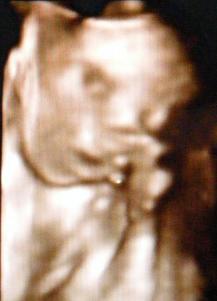

Betöltött 32. hét alkalmából teszek egy pocakfotót

A gondolkodó:)

A gondolkodó:)

Az alvó:)

Az alvó:)

A mosolygó:)

A mosolygó:)

A teli szájjal kacagó:)

A teli szájjal kacagó:)

A viszkető orrú:)

A viszkető orrú:)

A röhögős:)

A röhögős:)